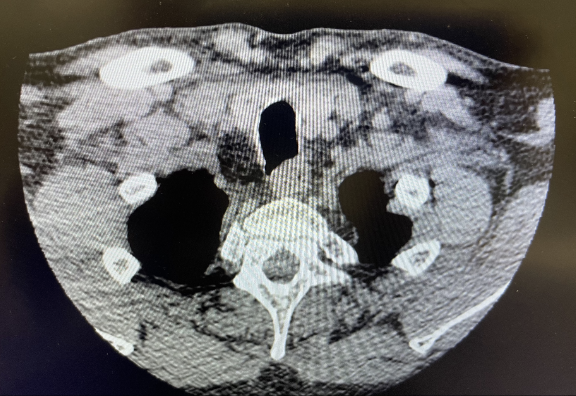

Foto de enmedio: forma de casa: luz glótica y cartílago tiroides que puede tener forma de lágrima o forma de reloj de arena.

Subglutis 3era foto huevito

TAC / AXIAL

NIVEL GLÓTICO:

CUERDAS VOCALES

Y CARTÍLAGO

TIROIDES